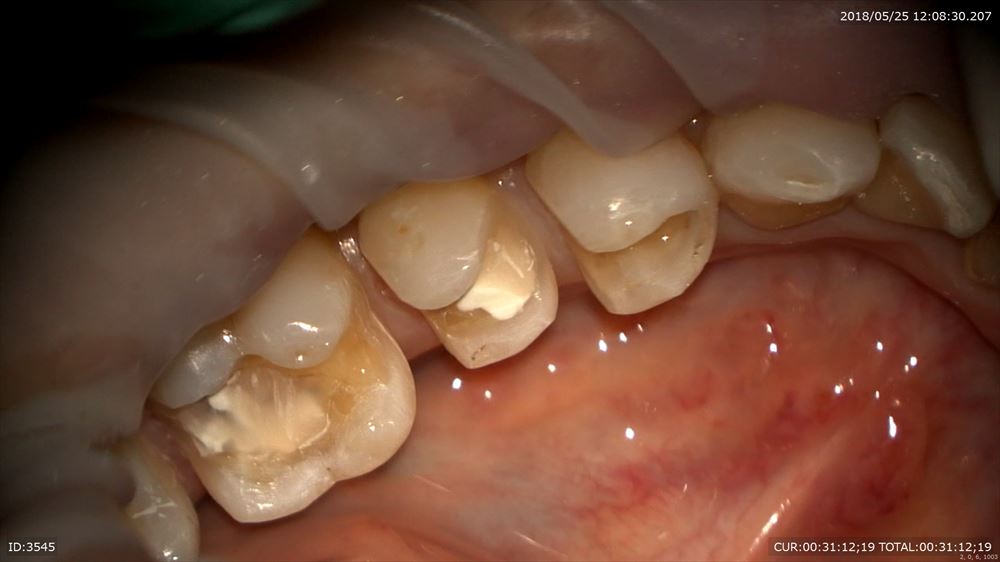

今日の修復。左下5番の修復。前回神経を保護したケース。

調整

セット

違和感も消えました。

歯茎の下までの虫歯も精密治療でこの様に2回で治ります。